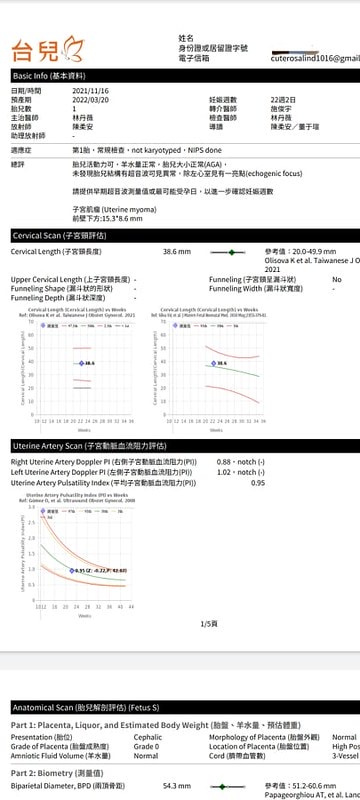

接下來就是解說報告時間

也不會很長,大概三五分鐘左右

簡單總評包括預產期估算、羊水量、胎兒活動力和大小

器官是否有異常、子宮動脈阻力,還有子宮頸長度和形狀等

小萊姆的高層次超音波照完之後

除了左心室有小白點之外

基本上其他都可以說是正常

但其實醫生說小白點也很常見

讓我不用太擔心!

總之結果應該是沒有大礙

不過我有發現有個子宮肌瘤

但據說是問題不大這樣

這個是紙本報告

會連動你的APP

所以手機上也看得到拉!